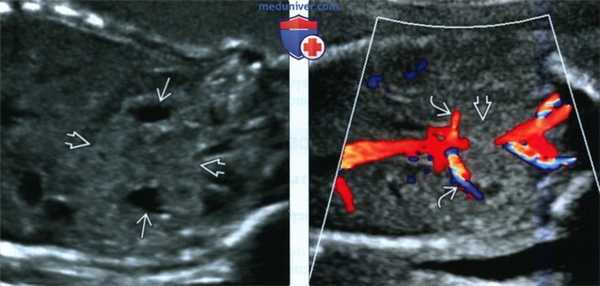

4. УЗИ:

• Исследование в режиме серой шкалы:

о Перешеек расположен впереди от позвоночника и прилегает к нижним полюсам противоположных почек

о Нижние полюса имеют изогнутую конфигурацию, а также удлиненные и плохо определяемые

о Форма перевернутого треугольника или грушевидная форма (продольное сканирование)

• ЦДК:

о Источники кровоснабжения вариабельны:

- Происходят от аорты или подвздошных артерий

- Реже - от нижней брыжеечной, срединной крестцовой или диафрагмальной артерии

о Венозный отток также варьирует

(Слева) Подковообразная почка может иметь вид объемного образования брюшной полости. Однако в паренхиме почки обнаруживаются гипоэхогенные пирамиды коркового вещества и более эхогенная кора. Лоханки подтверждают предположение, что в поле зрения на самом деле подковообразная почка.

(Справа) Другой случай. ЦДК. Патологическая извилистость почечных артерий связана с объемным воздействием со стороны перешейка слившихся почек.